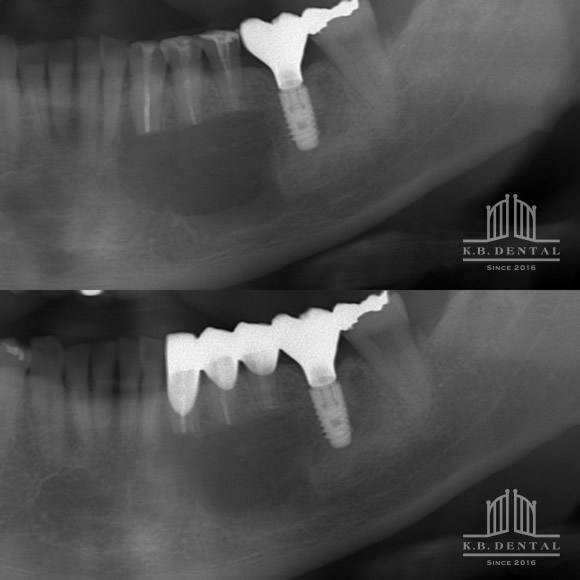

エナメル上皮腫(濾胞型)

術後2年経過の最も典型的なエナメル上皮種です。再発率が非常に高いので最低でも5年以上の経過観察が必要となります。今回は摘出術と一部健常域まで辺縁切除(骨を削る)を行いました。

1枚目(パノラマ)上:術前 下:術後 摘出部分に新生骨を認めます。

2枚目(CT)上:術前 下:術後 摘出部分に新生骨を認めます。